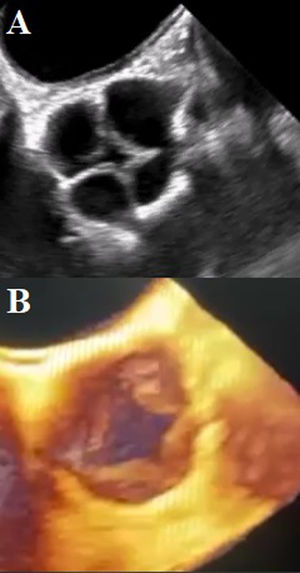

A transesophageal echocardiogram (TEE) was performed, showing a quadricuspid aortic valve with thickened cusps in their distal portion, right, left, and non-coronary cusps of the same size, with the presence of a small supernumerary cusp between the left and right coronary cusps. Aortic valve area by 3D of 2.5cm2. Central regurgitant jet reaching the apical portion of the left ventricle with an EROA of 0.44cm2 (Fig. 3).

(A) TEE mid-esophageal view in great vessels at 100 degrees. Showing quadricuspid aortic valve with thickened cusps. Commissural coaptation in an “X” shape in diastole. (B) 3D reconstruction of the quadricuspid aortic valve with a supernumerary cusp between the left and right coronary cusps.